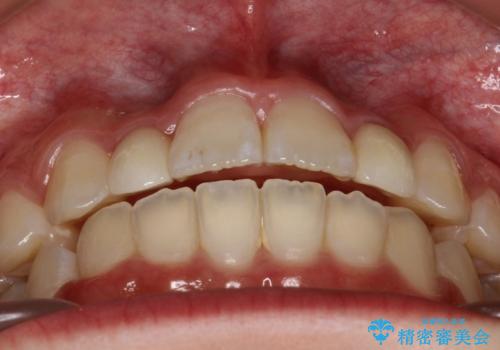

上あごの2番目の歯は矮小歯といって、生まれつき小さい歯となる事がよくあります。

このような場合、矯正によりスペースを集め、本来あるべき形態にセラミックで修正することもできます。

時間はかかりましたが、きれいな笑顔になりました。